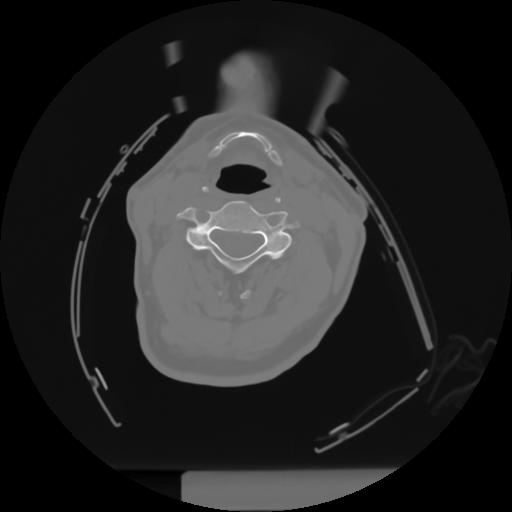

10 P.BLANDAS,,Axial,2.0,P.BLANDAS,,